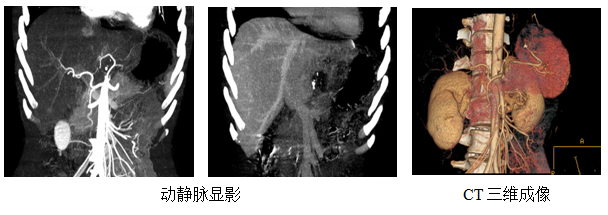

阿坝州人民医院是包括四川大学华西医院、四川省人民医院在内的全省四家“肝包虫病外科手术治疗国家救助项目”定点医院之一。外二科对肝包虫病的诊治水平在州内居领先水平。医院拥有先进的影像学技术,动静脉显影,为外科手术作精确指导;放射科CT三维成像,能够好更直观的了解病变位置及附近血管走形,更方便与患者家属沟通交流。